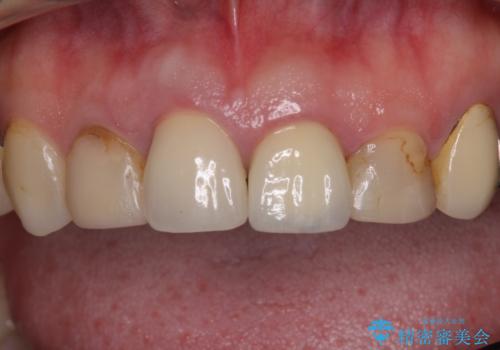

- 以前から前歯の根が折れていると言われていたものの放置しており、いよいよ痛みが気になってきたとのことで来院された患者様です。

検査の結果、右前歯の歯根が縦に破折していることが分かりました。

破折している歯は抜歯をし、歯肉が窪んでしまうので、傷口の治りを待って、歯肉移植を行うこととしました。

歯肉移植終了後、オールセラミックブリッジにて補綴することとしました。

歯肉移植により歯肉ラインや歯の形態を整えることができ、ブリッジによる補綴としたことで舞えば全体の色調を整えることができました。